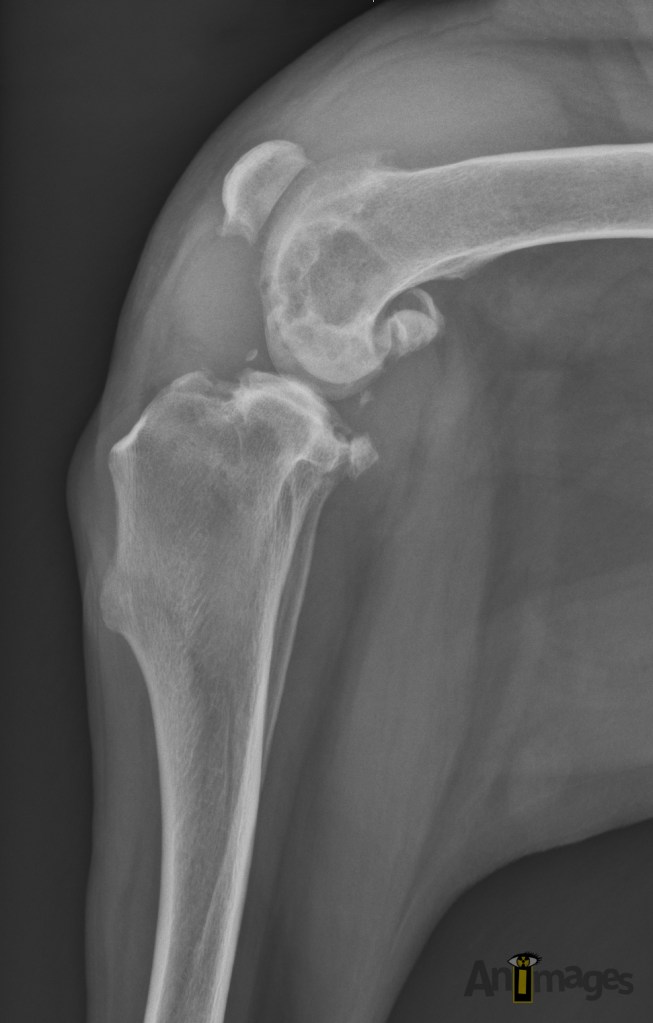

Latérale